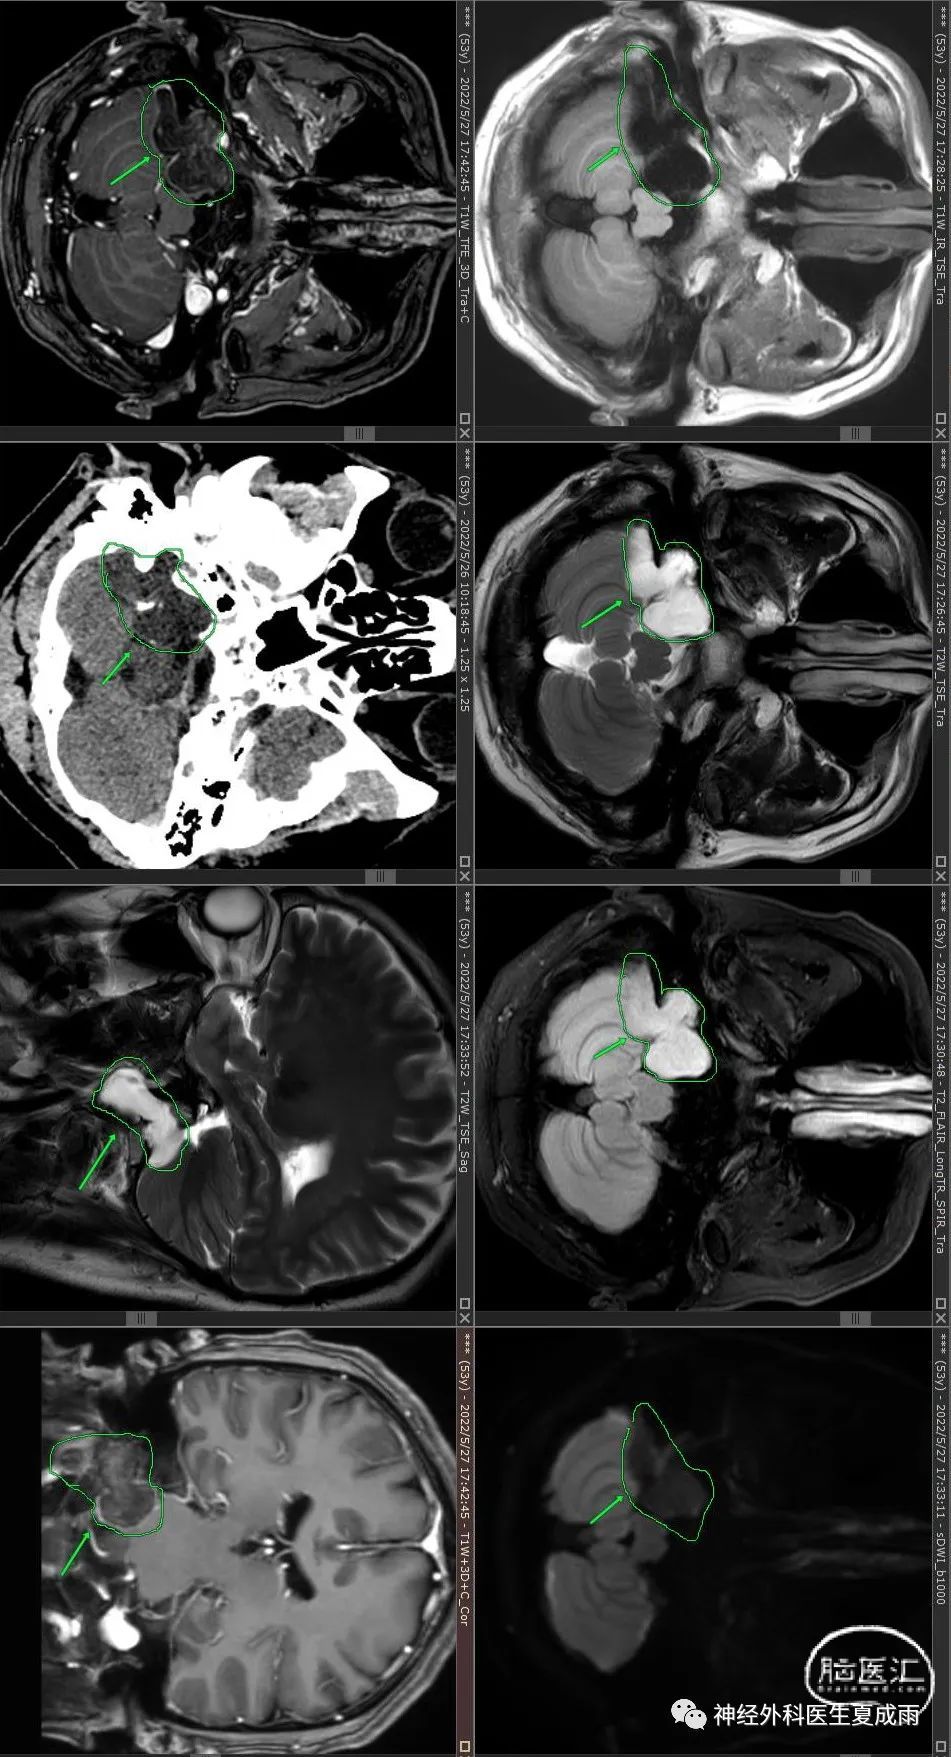

广东珠海市一名外科医生,男,53岁,2018年时因“头晕5~6年”在广州检查磁共振发现“颈静脉孔区占位”。

近2年逐渐出现声音嘶哑,吞咽困难,右肩疼痛,伸舌偏,在珠海及北京检查影像。

2022-5检查⏬

影像特点:肿瘤为颈静脉孔区颅内外沟通型占位,略有强化,周边及瘤内有钙化成分,肿瘤非钙化成分弥散略受限。

1.神经鞘瘤:虽然可以囊变,但内容物完全囊变、无实质成分的罕见,神经鞘瘤的实质成分强化一般比较明显。

2.脑膜瘤:一般强化明显,有脑膜尾征。

3.颈静脉球瘤:强化明显,磁共振T2可见血管流空影。

4.软骨肉瘤:病理是软骨基质内分布大小不一的软骨细胞和少数粘液样细胞,部分软骨有不规则钙化或骨化组织,因此影像学显示瘤内成分表现不均一,CT可见不同程度钙化或骨质,增强典型的呈蜂窝煤状。

5.脊索瘤:与软骨肉瘤表现类似,但主体多位于中线,起源于中线,再向侧方扩展侵袭。

6.转移癌:多有原发癌肿史,一般局部疼痛明显,进展快。

综合分析:该患者进展缓慢,结合其影像特点,考虑?决定行神经电生理监测下改良枕下远外侧入路颈静脉孔区肿瘤切除术。